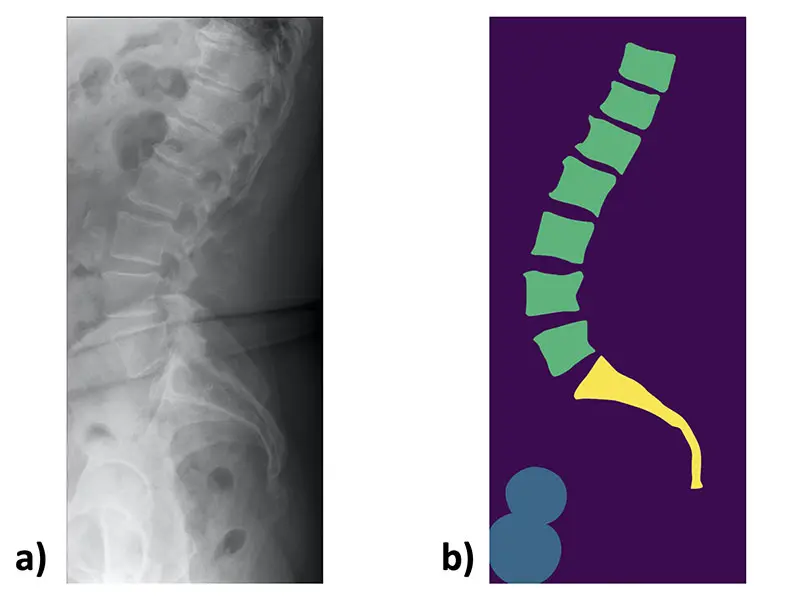

An example lateral lumbar radiograph a) and the corresponding manually created mask b)

b) An input image example.